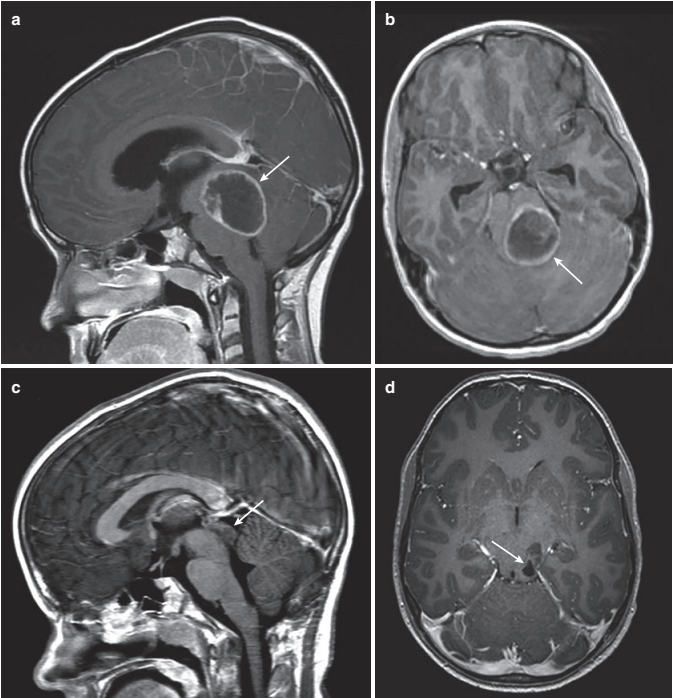

顶盖vs被盖:不同位置的中脑肿瘤有何不同?

脑干区肿瘤是一组发生于中脑、脑桥及延髓,并可向邻近小脑、颈髓区域发展的异质性病变。这类肿瘤在儿童中枢神经系统肿瘤中占比约为10%-20%,在成人中则占1.5%-2.5%。从病理类型看,最常见的是脑干胶质瘤,此外还包括海绵状血管瘤、转移性肿瘤以及淋巴瘤等。在发表于Springer Nature Switzerland AG 2019上的《Brainstem Tumors in Children》文章